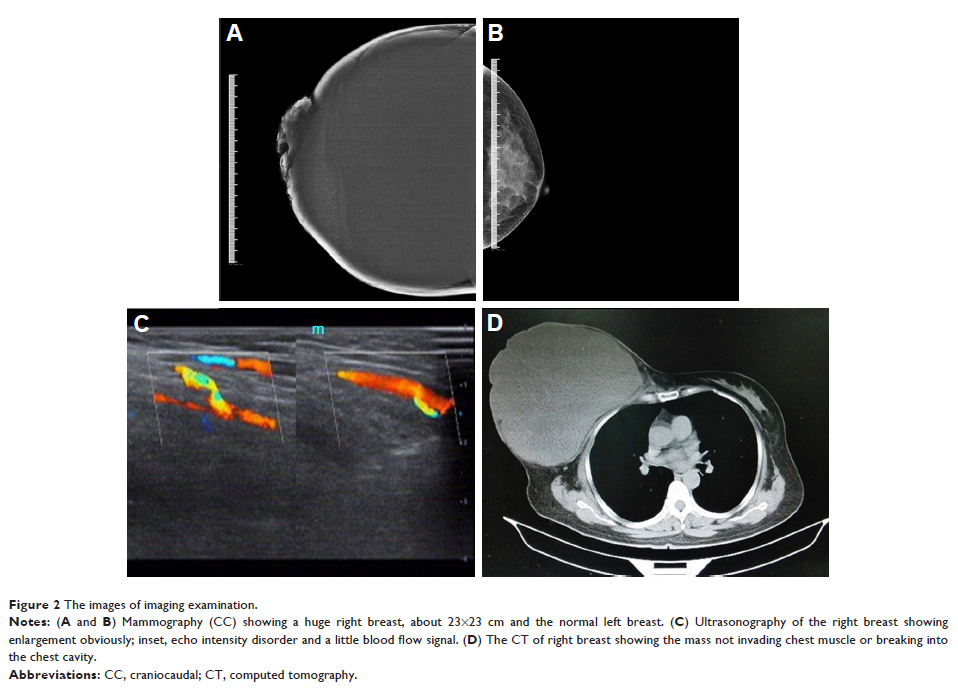

Case Report

- 作者:Yining Wang, Yonglin Zhang, Guanglei Chen, Fangming Liu, Chao Liu, Tiantian Xu, Zhenhai Ma

- 期刊:OncoTargets and Therapy